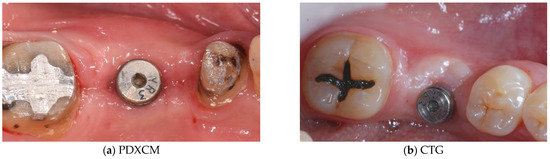

4. Discussion

5. Conclusions